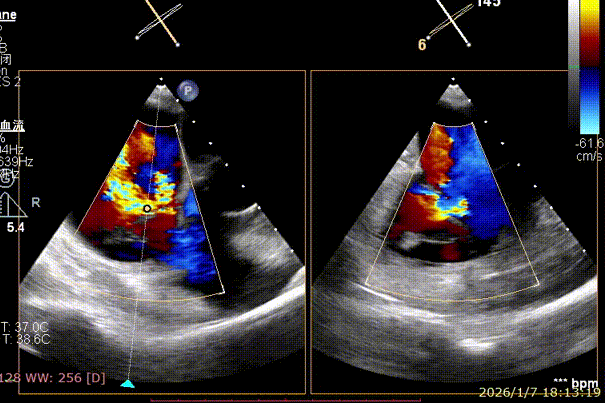

Preoperative precise assessment by transthoracic and transesophageal echocardiography (TTE/TEE) revealed:

Mitral valve: severe functional regurgitation (4+), effective regurgitant orifice area (EROA) 0.52 cm², regurgitant volume 68 mL.

Tricuspid valve: Type IIIb quadricuspid malformation with insufficiency, secondary severe regurgitation (4+), mild annular dilatation (mean diameter 40 mm), mean vena contracta 10 mm. Regurgitant orifices are located at anteroseptal, central, and posteroseptal regions, with marked enlargement of the right atrium and right ventricle.

Preoperative Imaging

Mitral regurgitation

3D color Doppler

Mitral valve Zone 2

Color Doppler of Mitral valve Zone 2